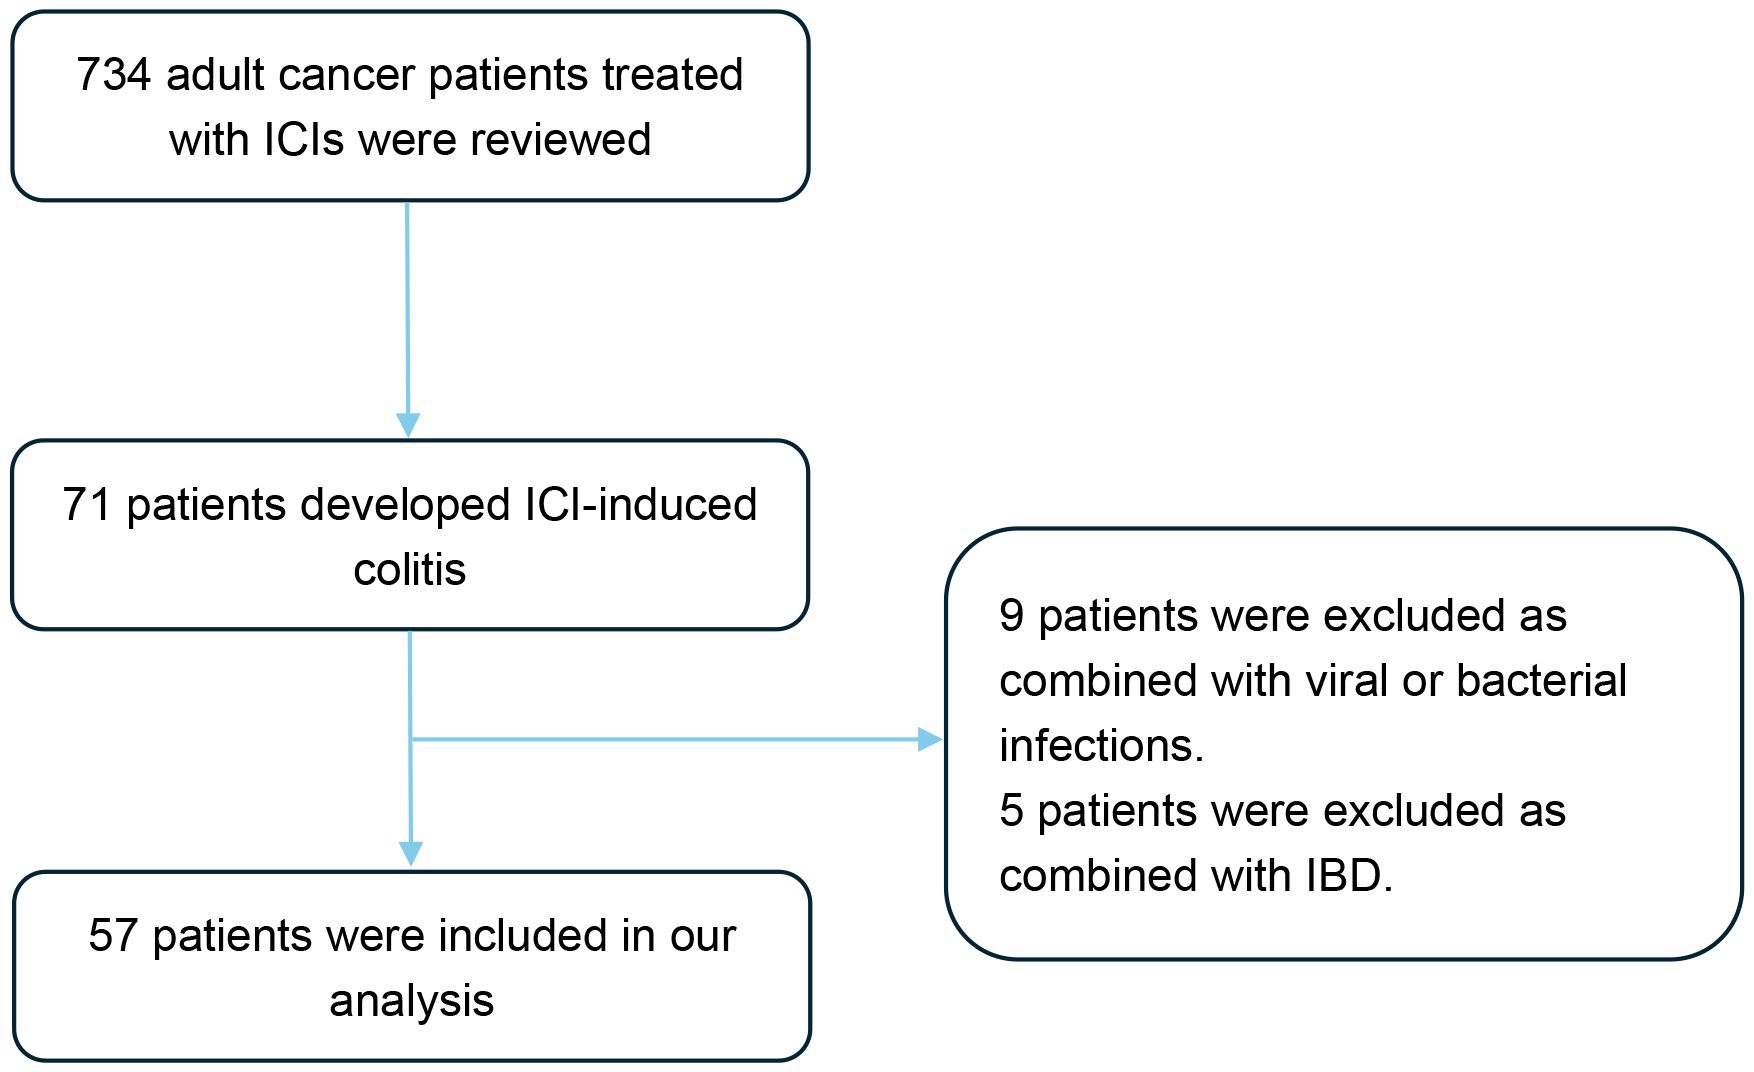

A total of 57 patients with ICI-induced colitis were included in this study (Figure 1). The patient’s characteristics are presented in Table 1A. The cohort comprised 41 males (71.9%) and 16 females (28.1%), with a median age of 60 years (interquartile range [IQR], 54-68). Gastrointestinal cancer represented the most common tumor type (40.4%), followed by lung cancer (26.3%), hepatobiliary cancer (15.8%), and pancreatic cancer (10.5%). Regarding the type of ICI treatment, 41 patients (71.9%) received anti-PD-1 monotherapy, 10 (17.5%) received anti-PD-L1 monotherapy, and 6 (10.5%) received combination therapy with anti-PD-1/PD-L1 and anti-CTLA-4 therapy. Colonoscopy was performed in 26 patients (45.6%). The median follow-up duration was 18 months (range, 2-79).

Figure 1. Flow diagram of the study design. A total of 734 patients were screened, of whom 57 patients met the eligibility criteria and were included in the final analysis. ICIs, Immune checkpoint inhibitors; IBD, Inflammatory bowel disease.

ICI-induced colitis-related information

The characteristics of ICI-induced colitis are presented in Tables 1B, C. The median time to onset of colitis was 103 days (interquartile range [IQR] 52–142 days). The median number of ICI treatments received by patients before the onset of colitis was 5 (IQR 2-8). Diarrhea was the predominant symptom (n = 54, 94.7%), with many patients also experiencing abdominal pain (n = 32, 56.1%) or bloody stool (n = 28, 49.1%). Fever was observed in 5 patients (8.8%) at diagnosis. Among all patients, the number of cases with grade 2, 3, and 4 diarrhea was 17 (29.8%), 29 (50.9%), and 4 (7.0%), respectively. The number of cases with grade 2, 3, and 4 colitis was 39 (68.4%), 2 (3.5%), and 3 (5.3%), respectively. It is important to note that the grades of diarrhea and colitis may not be entirely consistent in many patients with ICI-induced colitis. Among the 26 patients who underwent colonoscopy, 10 patients (38.5%) showed non-ulcerative inflammation (such as mucosal edema, erythema, loss of vascular pattern, or increased friability, Figures 2A, B), while 16 patients (61.5%) presented with ulcerative lesions (Figures 2C, D). In terms of distribution, pan-colonic involvement was observed in 16 patients (61.5%), whereas partial colonic involvement (confined to either the left or right colon) was observed in 10 patients (38.5%).

Figure 2. Endoscopic features in patients with ICI-induced colitis. (A) Diffuse mucosal erythema with increased friability. (B) Mucosal edema, exudate and loss of vascular pattern. (C, D) Multiple ulcerative lesions.